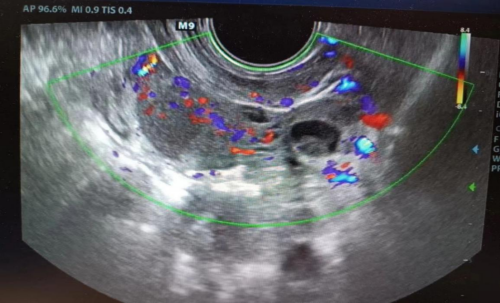

就诊,入院时由于腹痛剧烈,小雨已经无法正常行走。完善经直肠盆腔彩超后,提其左侧输卵管积液,左侧附件区类“漩涡”样回声,疑输卵管发生扭转,小雨马上被收入妇科住院。

接诊医生廖年春与患儿家长积极沟通并取得其同意后,第一时间为小雨行全麻下“腹腔镜探查术”。术中发现左侧输卵管积液、增粗,直径约5cm,扭转5圈,相当于扭转了1800°,其远端呈暗红色缺血缺氧表现,幸亏入院及时,不然有可能发生输卵管缺血坏死!手术医生将扭转的左侧输卵管进行复位,恢复正常血运,并对输卵管进行修复,完好地保留住了附件。术后,小雨没再出现腹痛的情况,3天后痊愈出院。